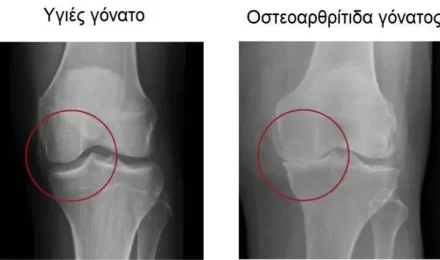

Οστεοαρθρίτιδα – πάθηση που επηρεάζει τις αρθρώσεις

Οστεοαρθρίτιδα Η οστεοαρθρίτιδα είναι πάθηση που επηρεάζει τις αρθρώσεις, προκαλώντας πόνο και δυσκαμψία.